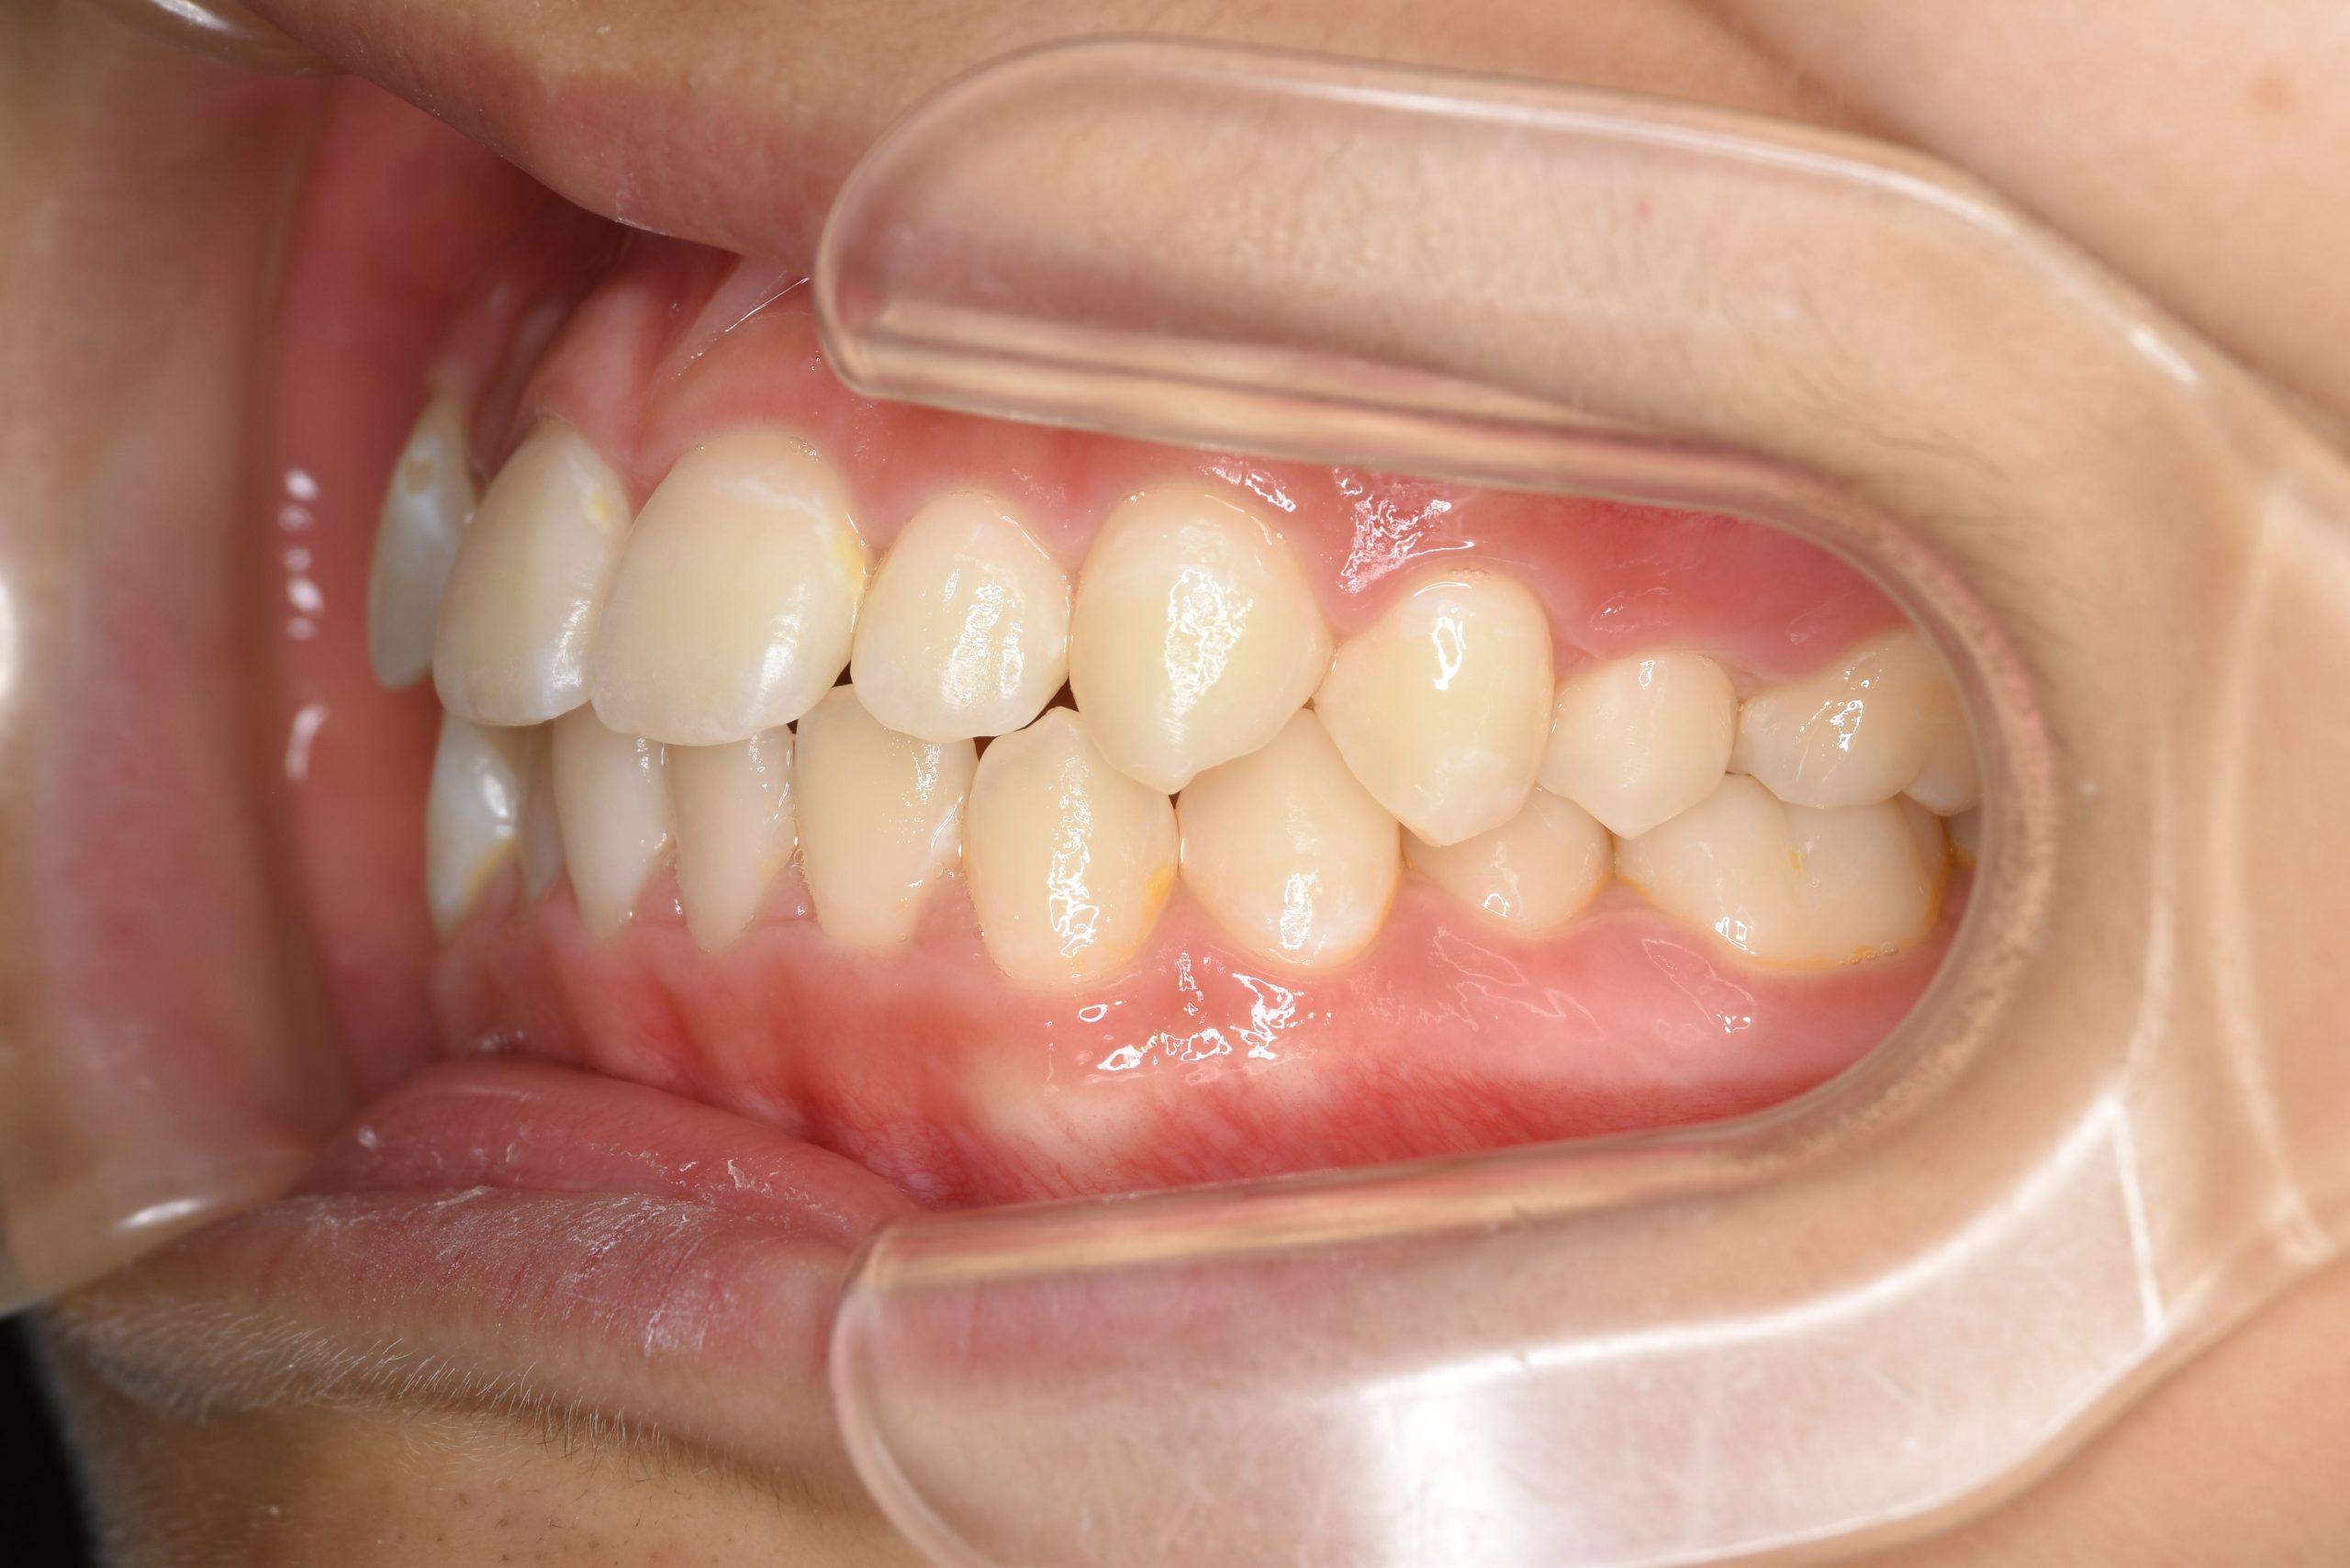

アフター

子どもの矯正治療|症例_169

施術内容 上顎急速拡大装置と下顎リンガルアーチを用いて上下顎骨を拡大した。

その後マウスピース型矯正装置で歯牙を配列し良好な咬合を獲得した。

治癒期間 3年5ヶ月間